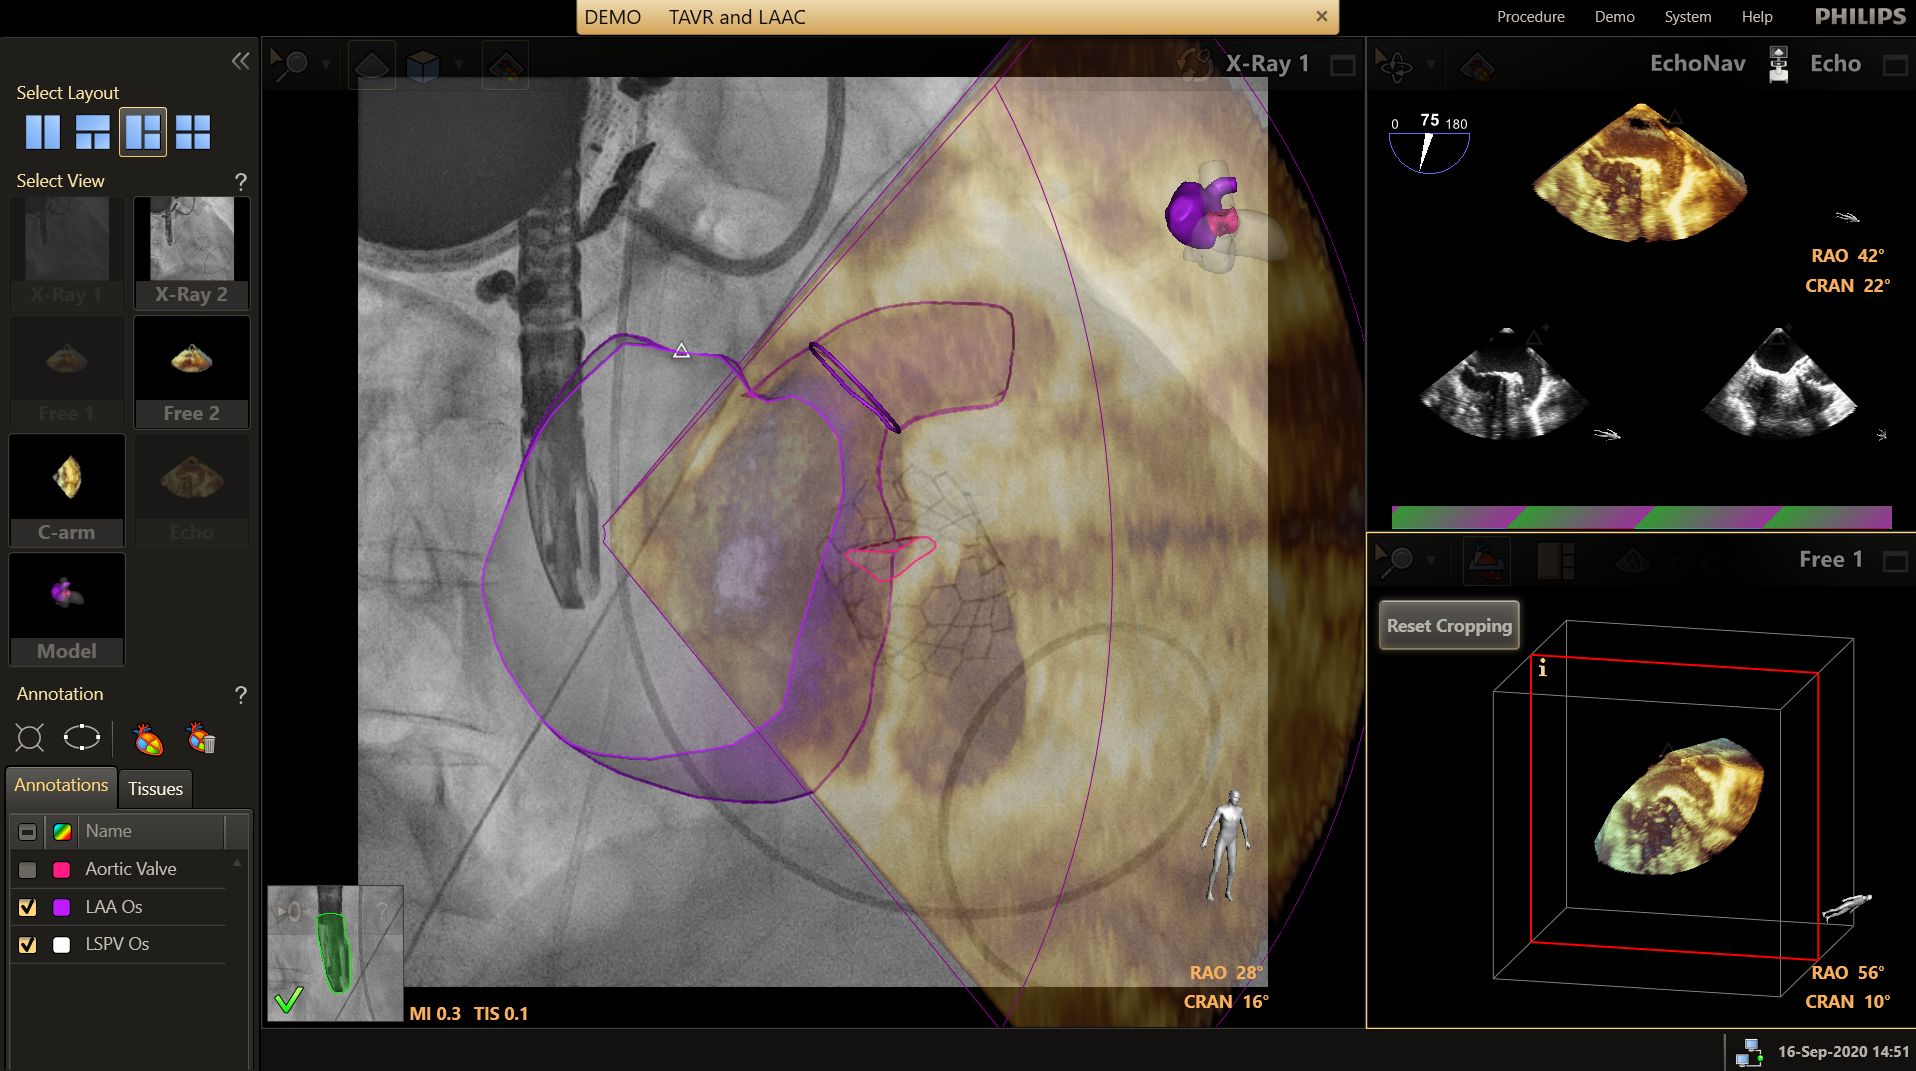

less transseptal puncture time

Echonavigator reduces transseptal procedure time[2].